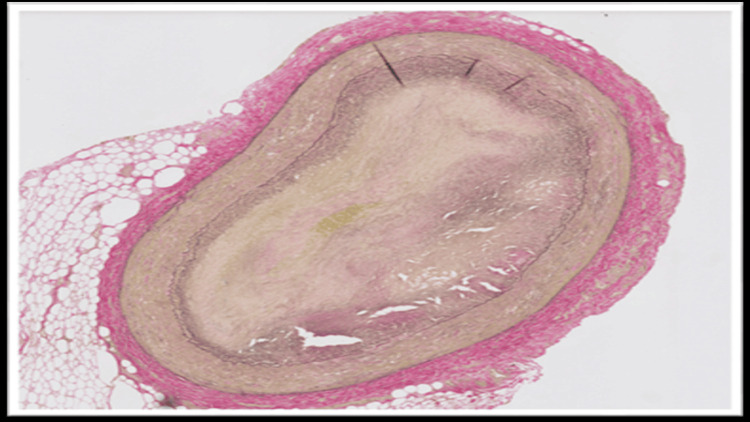

The blood and vitreous fluid were collected for toxicology analysis. Microscopic examination of the heart showed a complete occlusion (100%) of the proximal portion of the left anterior descending coronary artery due to an organized thrombus (Figure 1). A trichrome stain was performed, which showed fibroblastic growth within the thrombus (Figure 2). Elastic stain performed on the section revealed a focus of disruption of the internal elastic lamina (Figure 3). The rest of the anterior descending coronary artery, the left circumflex artery, and the right coronary artery showed normal caliber with no evidence of thrombus or atherosclerosis. A focal area of scarring was identified in the interventricular septum and left ventricle. The right ventricular wall showed a subendocardial scar. No evidence of acute myocardial infarction (e.g., myocyte necrosis, contraction band necrosis, wavy fibers, or early neutrophilic infiltration) was identified in the sections from the right and left ventricles. The abdominal aorta showed no atherosclerotic changes. Sections from the liver showed moderate macrovesicular steatosis. No fibrosis was identified.

In fatal cases of non-atherosclerotic coronary thrombosis, the diagnosis is established primarily through autopsy and postmortem toxicology analysis. Gross examination may not reveal significant atherosclerosis in these cases. Histopathological examination of the coronaries may reveal occlusion of the artery by thrombus. However, the possibility of a postmortem thrombus can be ruled out in such cases by doing ancillary studies like trichrome stain, which confirms fibroblast growth within the thrombus, and elastin stain, which reveals disruption of the internal elastic lamina, thereby favoring antemortem thrombus development. These histopathological findings, along with elevated levels of THC and its metabolites, can help in ruling out other causes of SCD, such as vasculitis or atherosclerosis, and thereby identifying the cause of death.